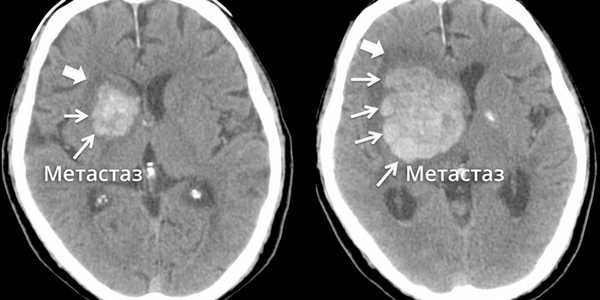

Метастазы головного мозга, фото. На КТ с контрастным усилением у пожилой пациентки (в верхнем ряду слева) с жалобами на головные боли выявлены множественные объемные образования в левом полушарии мозга, интенсивно накапливающие контрастное вещество. Образования имеют характерную форму в виде «кольца». На изображениях в нижнем ряду и вверху справа определяются множественные очаги в головном мозге: отчетливо видны округлые образования с более плотным «ободком» по периферии, располагающиеся в левой теменной доле.

Как выглядят метастазы в головной мозг на компьютерной томографии (КТ)? Практически во всех случаях выявляется единичное (реже) либо множественные (чаще) объемные образования, которые отвечают следующим параметрам:

- Форма неправильная или сферическая

- Структура неоднородная, в центре очага может обнаруживаться область низкой плотности, обусловленная некрозом и распадом центральной части опухоли. По периферии — более плотный «ободок», который отражает активную часть опухоли, имеющую кровеносные сосуды и обладающую способностью к росту. Этот «ободок» окружен зоной низкой плотности, отражающей отек ткани мозга. Ширина данной зоны может быть различной — от нескольких мм до нескольких десятков см. Относительно однородная структура без наличия участка низкой плотности в центре и без перифокального отека. Такая структура метастаза свидетельствует о его относительной «доброкачественности»

- Отношение к прилежащим мозговым структурам. Очаги могут оказывать объемное воздействие различной степени выраженности на прилежащие отделы мозга, вызывая их смещение. Например, объемное образование в височной доле чаще всего приводит к выбуханию гиппокампа под намет мозжечка (височно-тенториальная дислокация), объемное образование мозжечка может воздействовать на мозговой ствол, приводя к его сдавлению, и т. д. Смерть при метастазах в мозг может наступить в результате сдавления мозгового ствола и нарушения дыхания и сердечной деятельности. В зависимости от локализации, вторичные очаги могут приводить к сдавлению церебральной ликворной системы, приводя к развитию окклюзионной гидроцефалии (резкому расширению центральных ликворных пространств на фоне повышения внутримозгового давления при окклюзии путей оттока ликвора из полости черепа)

- Тип роста. Метастазы могут обладать инфильтративным типом роста (расти, разрушая окружающие ткани) и экспансивным типом (расти, раздвигая окружающие ткани). В первом случае они чаще всего дают осложнения в виде кровоизлияния, то во втором обычно обуславливают возникновение дислокаций.

- Параметры контрастного усиления. Типичные вторичные опухоли в головном мозге увеличивают свою плотность в периферических отделах при внутривенном введении контраста, принимая вид «кольца», «полукольца», «спирали». Гораздо реже наблюдается равномерное контрастное усиление очага. Обычно центральная зона опухоли не усиливается, как и область перифокального отека.